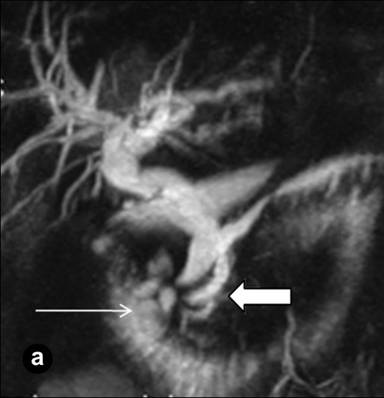

A 43-year-old man with abdominal pain of a one year duration, nausea, vomiting, weight loss and intermittent jaundice was referred to the Hospital of the Russian Federal Security Service, Moscow, Russia, with a clinical diagnosis of chronic pancreatitis. The patient had a history of previous extensive small bowel resection; one year previously he had been operated on for acute pancreatitis with abdominal draining and a cholecystectomy. The epigastrium was mildly sensitive on physical examination. The laboratory findings were normal, except for a slight increase in the bilirubin level (40 µmol/L; reference range: 3.5-19.0 µmol/L). Abdominal US showed diffuse changes of the liver and pancreas. On computed tomography (Figure 6) and magnetic resonance imaging (Figure 7), a thick-walled cystic lesion 4x4.5 cm which had infiltrated the medial wall of the second part of the duodenum was observed against the background of the minimally changed pancreatic structure with pancreatic and common bile duct dilation,. Endosonography revealed a solid and septated cystic lesion mainly located in the submucosa of the narrowed second portion of the duodenal wall.

Figure 7. Magnetic resonance imaging (Case #2). (a.) Magnetic resonance cholangiopancreatography; (b.) Balanced turbo field echo (B-TFE). A septated cyst is located in the medial wall of the second part of the duodenum (long arrows) causing biliary and pancreatic hypertension (large arrow). Stenosis of the terminal parts of the common and the main pancreatic ducts (short white arrow). Scheme of the lesion and unaffected pancreas is in the upper right corner. |

|